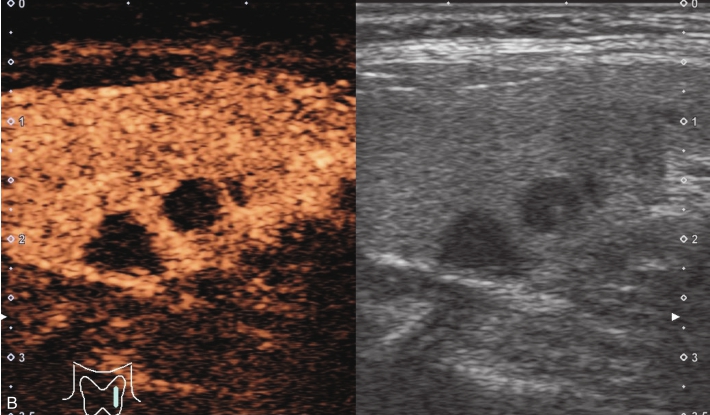

图1-3-9 结节性甲状腺肿常规超声声像图

A.甲状腺左叶纵切面;B.CDFI血流图

甲状腺左叶中部结节15s开始增强。增强早期与周围正常甲状腺组织呈同步等增强,内部增强不均匀,增强后结节边界清,形态规则,周边可见环状高增强,增强晚期呈不均匀性低增强,见图1-3-10、ER1-3-5。

结节性甲状腺肿超声造影表现为病变多与周围正常甲状腺组织呈同步等或高增强,增强多较均匀,伴有囊性变者,内部可见无增强区,增强后结节边界清,周边可见环状增强,增强晚期呈等或稍高增强,也可呈稍低增强。

图1-3-10 结节性甲状腺肿超声造影图

A.增强早期结节呈同步不均匀性等增强;B.增强晚期呈不均匀性低增强